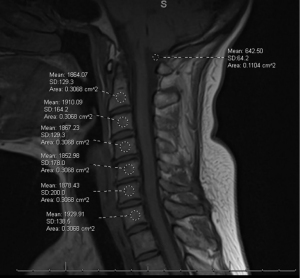

Preoperative cervical MRI was reviewed when available to calculate the C-VBQ score. ROIs were placed within the cancellous portion of the vertebral bodies from C2 through C7 on sagittal T1-weighted images, avoiding cortical bone, endplates, and focal sclerosis. Mean signal intensity (SI) across C2–C7 vertebral ROIs was calculated and normalized to cerebrospinal fluid (CSF) SI measured at the level of the cisterna magna to generate a C-VBQ score. Two independent observers performed measurements, and interobserver reliability was assessed using the ICC. Figure 3 demonstrates ROI placement methodology.

C-VBQ was inversely correlated with CT-derived HU values across cervical levels (C2–C7), indicating that higher VBQ (worse bone quality) corresponded to lower HU. Statistically significant inverse correlations were observed at multiple levels, supporting convergent validity between MRI-based VBQ and CT-based HU as opportunistic measures of vertebral bone quality. Baseline characteristics did not differ significantly between patients with and without available preoperative MRI detailed in Table 1. HU-VBQ correlations are reported in Table 4, and ROI methodology is illustrated in Figure 3. Exploratory correlations between cervical HU at each vertebral level and 1-year patient-reported outcome scores are detailed in Table 7.